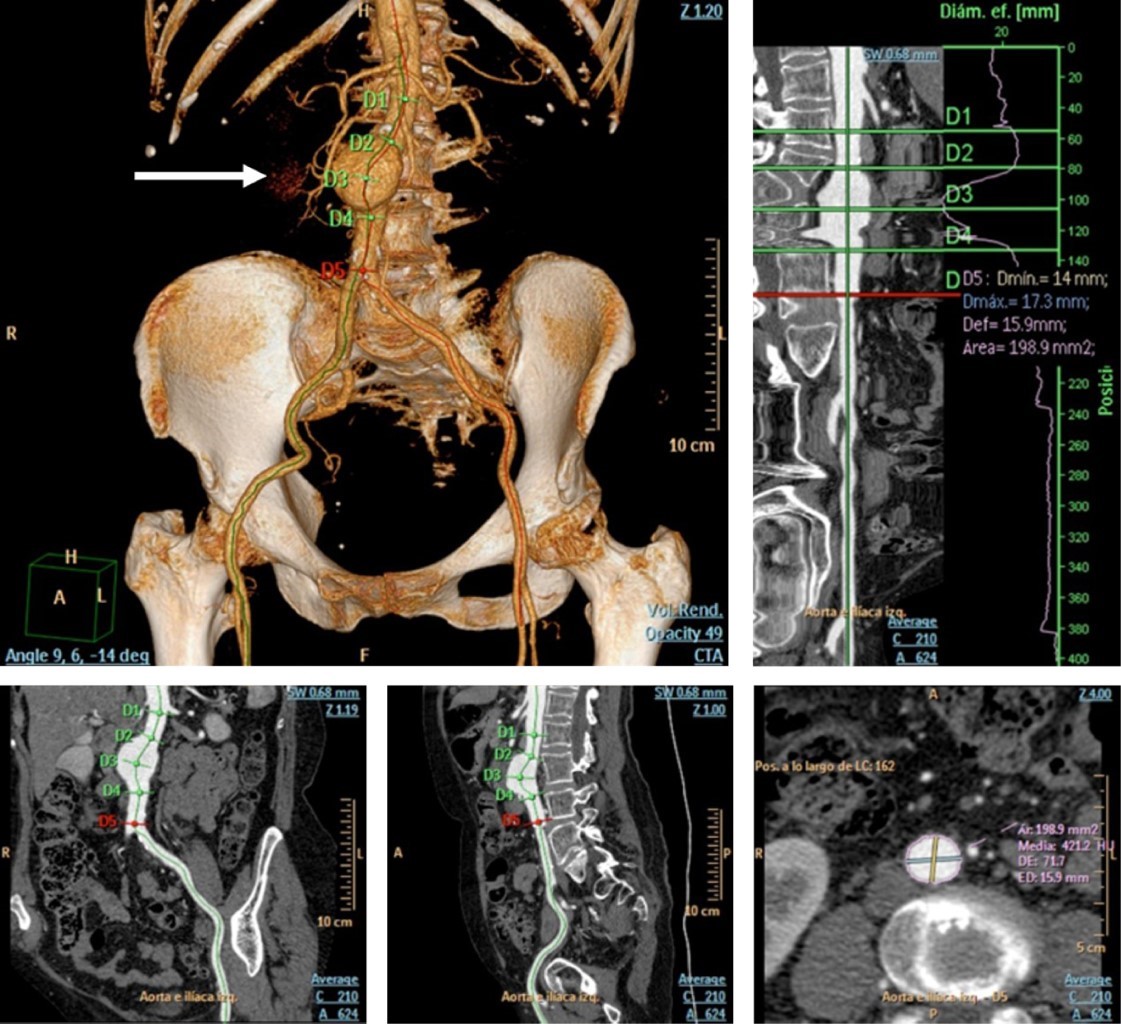

Abdominal Aortic Aneurysm (AAA) is a potentially fatal pathology, present in 2-4% of the population over 50 years of age. Angiotomography (CTA) allows localization of AAA, determines its length, the involvement of visceral branches and flow characteristics. Currently CTA is used to plan endovascular treatment. Treatment depends on the size and location of the aneurysm, age, renal function and other conditions. Aneurysms smaller than five centimeters in diameter are usually monitored by ultrasound or CT every six to 12 months. Surgical treatment is recommended in aneurysms with a diameter greater than 5 centimeters; the risk of rupture is four times higher in women. As a cultural fact of interest, the physicist Albert Einstein died of AAA rupture on April 18, 1955.

Figure 2